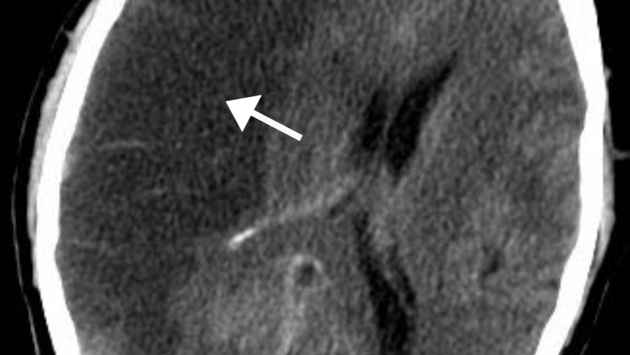

В эксперименте участвовало 54 животных. Половину из них (27 крыс) в течение двух месяцев кормили рационом, в котором жиры составляли 11% от всех соединений, белки — 24%, а углеводы — 65%. Еще 27 крыс такое же время содержали на кетогенной диете с 84% жиров, 11% белков и 5% углеводов. После этого у 19 грызунов из каждой группы питания искусственно пережимали среднюю мозговую артерию — сосуд, который поставляет кровь в боковые зоны коры мозга. Таким образом авторы смоделировали ишемический инсульт.

Спустя две недели после вмешательства биологи проанализировали активность генов в головном мозге крыс, чтобы понять, как изменились обменные процессы в тканях при разных режимах питания, а также после инсульта. Оказалось, что при обоих вариантах диеты инсульт привел к значительным перестройкам: при углеводной диете изменилась активность 10 449 генов, а при кетогенной — 11 389. Анализ показал, что сильнее всего инсульт активировал группы генов, участвующих в запуске воспаления, иммунном ответе, контроле сосудистой системы и развитии стволовых клеток. Все это указывает на то, что в результате ишемического инсульта при обоих типах рациона в мозге развивается воспаление.

Кроме того, исследование ткани мозга и наблюдение за поведением животных показали, что кетогенная диета не повлияла на объем повреждения и скорость восстановления двигательных функций у крыс после инсульта.